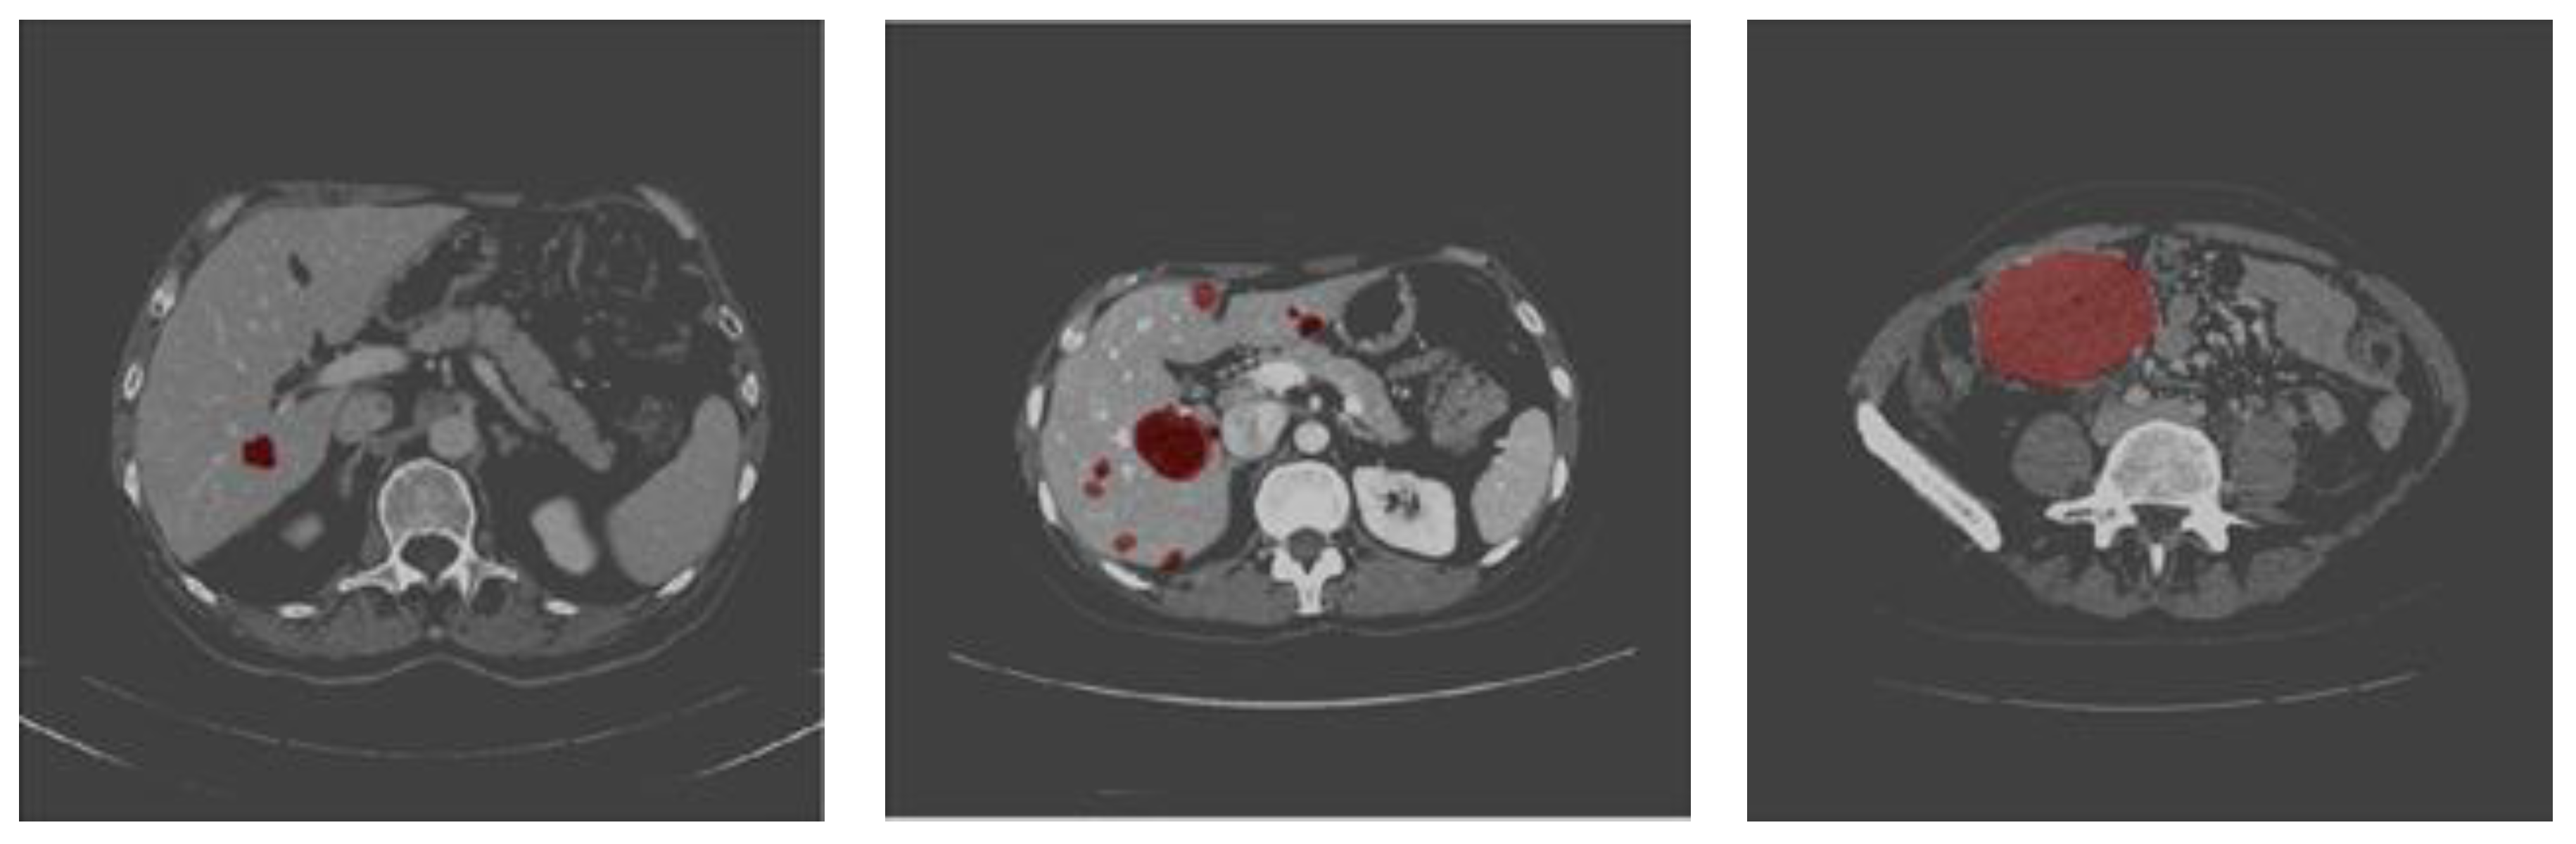

Liver Tumor Segmentation in CT Scans Using Modified SegNet

3. Materials and Method

3.1. Dataset